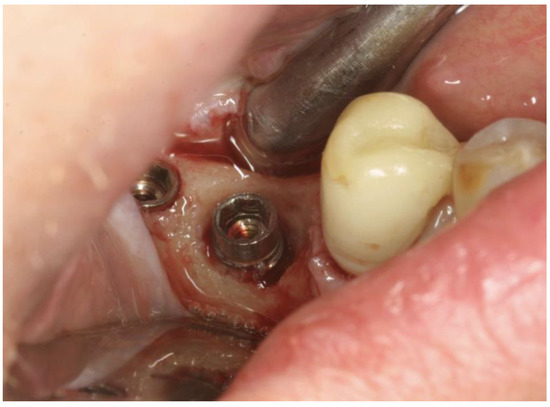

Then, the OHLLT protocol was performed (Wiser diode laser, Sioxyl Solution, Doctor Smile, Vicenza, Italy) (Figure 4): irrigation of peri-implant pockets with Sioxyl Solution; aspiration of Sioxyl Solution emerging from the gingival sulcus and leaving the remaining solution inside the pocket for 2 min; introduction of the HF Diode Laser Fiber 400 microns within the pocket and reaching the bottom, radiation of subgingival tissues with a back and forth movement using the dedicated program, 60 s per side (2.5 W peak power, high frequency, 10 KHz, power average 0.5 W, fluency 25,000 J/cm2, 416.66 J/cm2 per second). After the decontamination with OHLLT, the site was grafted with a mix of Bio-Oss granules 25, autologous bone chips, platelet-rich fibrin (PRF) and collagen membranes (45% Bio-Oss 25, 45% PRF, 10% autologous bone chips). At the end, we carried out flap repositioning and suturing.

Figure 4. HF diode laser, tip 400 microns, peak power 2.5 Watt, average power 0.5 Watt, T-on 20 microseconds, T-off 80 microseconds, frequency 10 KHz (Wiser, Doctor Smile) with Sioxyl Solution (stabilized H2O2 10 vol. 3%).